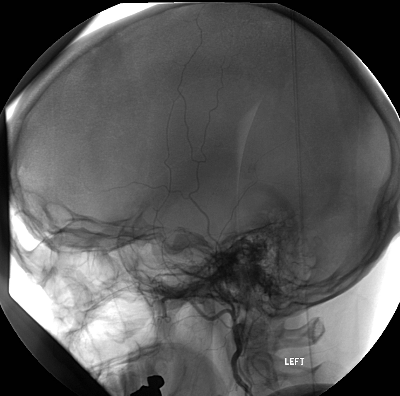

Direkte Fistel zwischen A. carotis und Sinus cavernosus nach Schädel-Hirn-Trauma mit Schädelbasisfraktur. Präinterventionell rechte A. carotis interna selektiv dargestellt in p.a.-Projektion. Unmittelbar nach Kontrastmittelinjektion kommt es zum Kontrastmittelübertritt in den Sinus cavernosus und arterialisierte ableitende Venen.

Kontrolle nach transarteriellem Fistelverschluss

Kontrolle nach Coiling der Fistel. Gleiche Darstellung wie präinterventionell, selektive Injektion der rechten A. carotis interna in p.a.-Projektion. Nun nahezu vollständig verschlossenen Fistel. Keine Füllung des Sinus cavernosus mehr. Keine Steal-Effekte. Nun regelrechte Füllung der intrakraniellen Arterien.